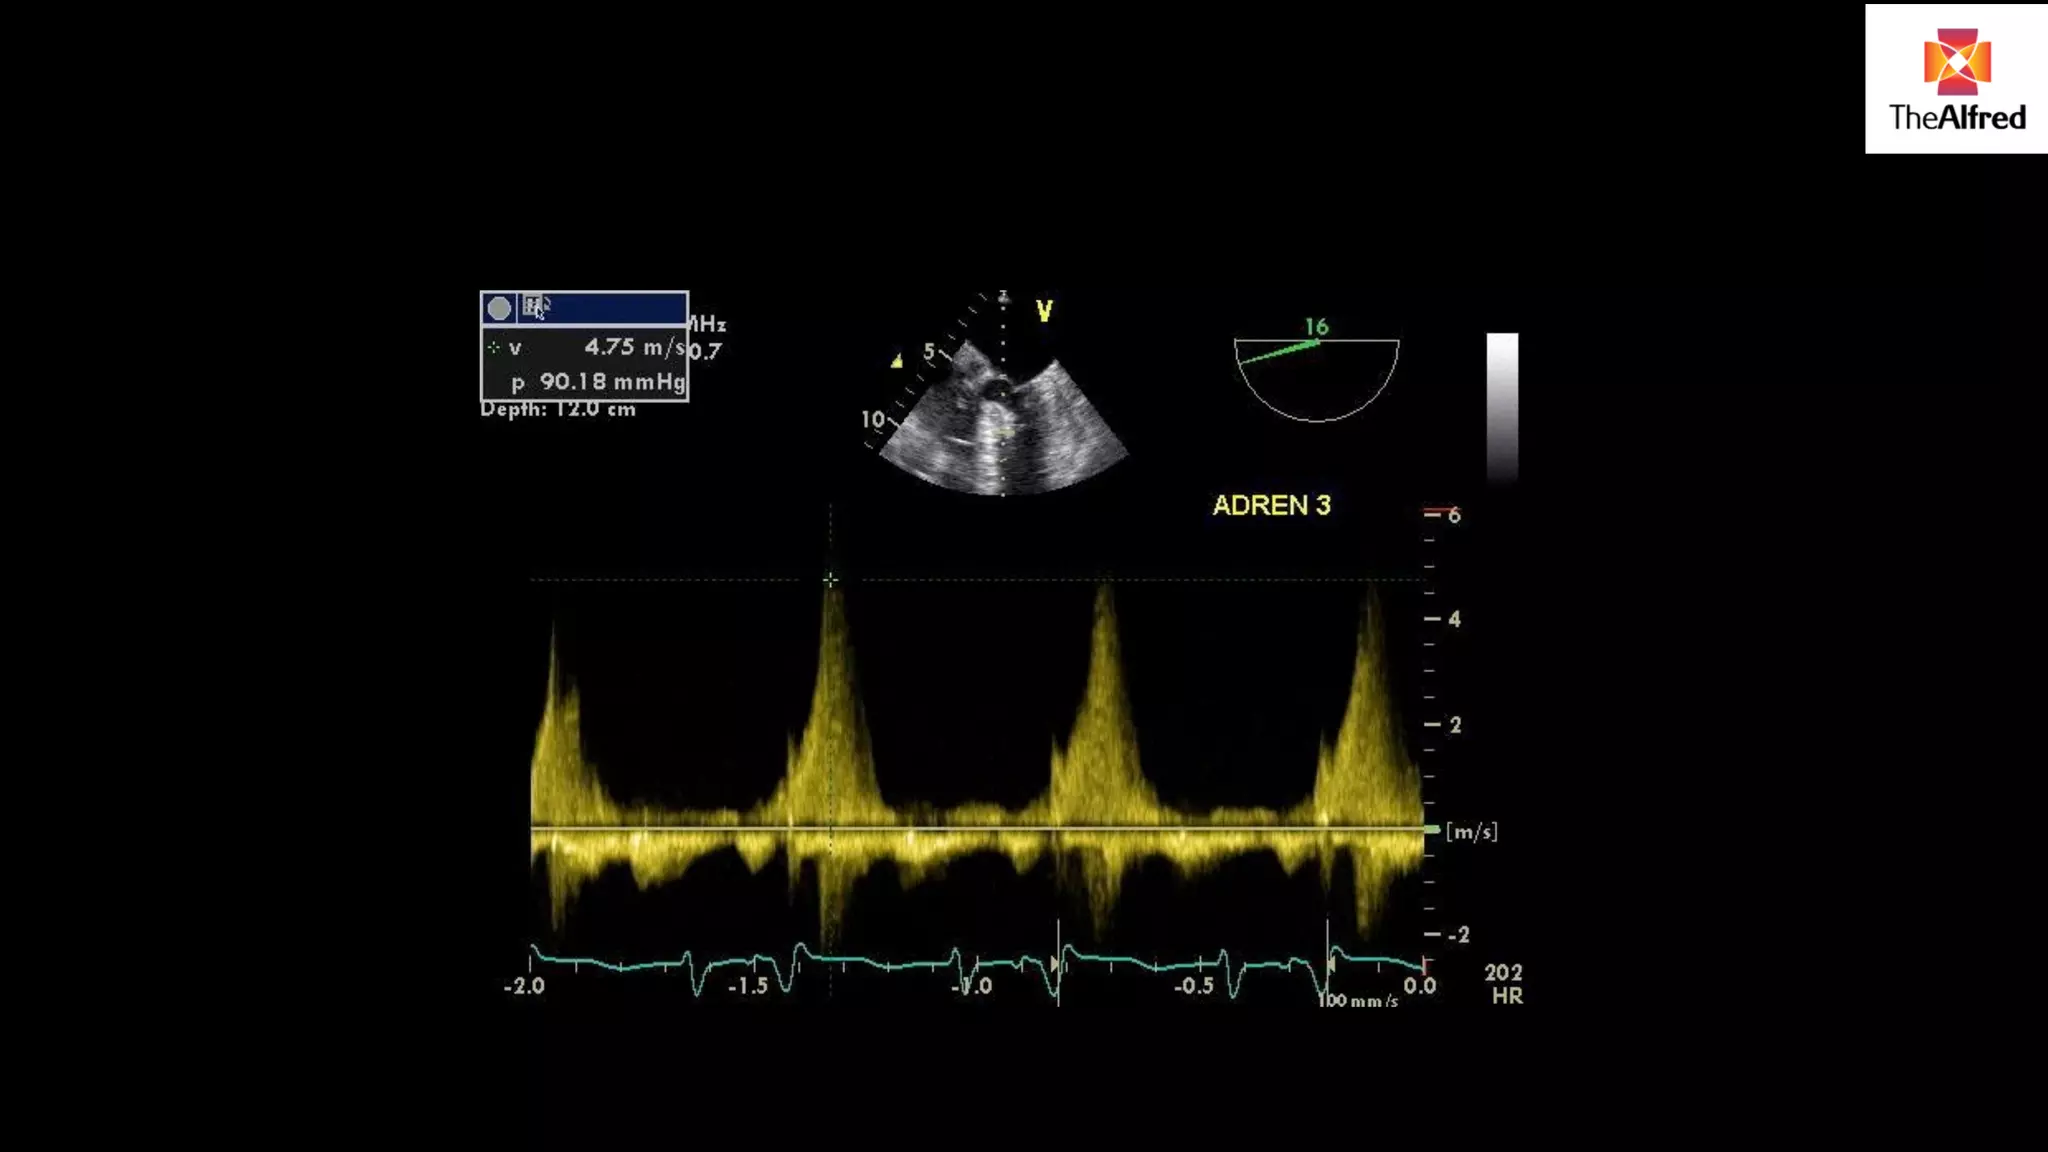

HOW DO YOU KNOW YOU’VE GOT A

GOOD DOPPLER TRACE

PW Doppler spectral

outline

Trace not “filled in”- in

moving front of blood flow

Not jagged feathery ends

Measurement of VTI or

stroke distance

Average 3 in sinus rhythm

Average 5 if arrhythmia

LVOT method Assumesthe LVOT is a cylinder We can measure the VTI of blood flow in the LVOT by placing a pulse wave doppler gate in LVOT This gives us the LVOT VTI

Major pitfalls ! Flow acceleration at valve-measure 1 cm back Ensure line up with cursor-inaccurate if >10°

USE VIEW WITHTHE BEST DOPPLER LINE UP- DIFFERENT FOR DIFFERENT PATIENTS 5 chamber view 3 chamber view

HOW DO YOUKNOW YOU’VE GOT A GOOD DOPPLER TRACE PW Doppler spectral outline Trace not “filled in”- in moving front of blood flow Not jagged feathery ends

Measurement of VTIor stroke distance Average 3 in sinus rhythm Average 5 if arrhythmia

Patient commenced onadrenaline after study LVOT measured at 1.0 cm, VTI N LVOT in adult 1.8-2.6